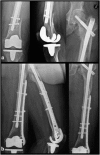

Osteoporotic distal femur fractures in the elderly: peculiarities and treatment strategies

Distal femur fractures account for 4-6% of osteoporosis related fractures of the femur in the elderly population. They represent a relevant cause of morbidity and mortality in the geriatric population with a reported 1-year mortality reaching 30%. Non-displaced fractures or even displaced fractures in patients with high operative risk can be treated conservatively. However, operative treatment is the most widely accepted management option for displaced fractures. The advantage resides in early mobilization and weight-bearing, reducing risks related with a prolonged immobilization when compared with conservative treatment. On the other hand, the intrinsic difficulty of fixing an osteoporotic bone is a major concern. The presence of osteosynthesis devices or prosthetic implants in the femur can make the surgical treatment more challenging, sometimes limiting therapeutic options. Aim of the present paper is to review the most recent literature about osteoporotic distal femur fractures in the elderly, including periprosthetic and other hardware related fractures, to highlight current evidence on management options and related results as a guide for the daily clinical practice.